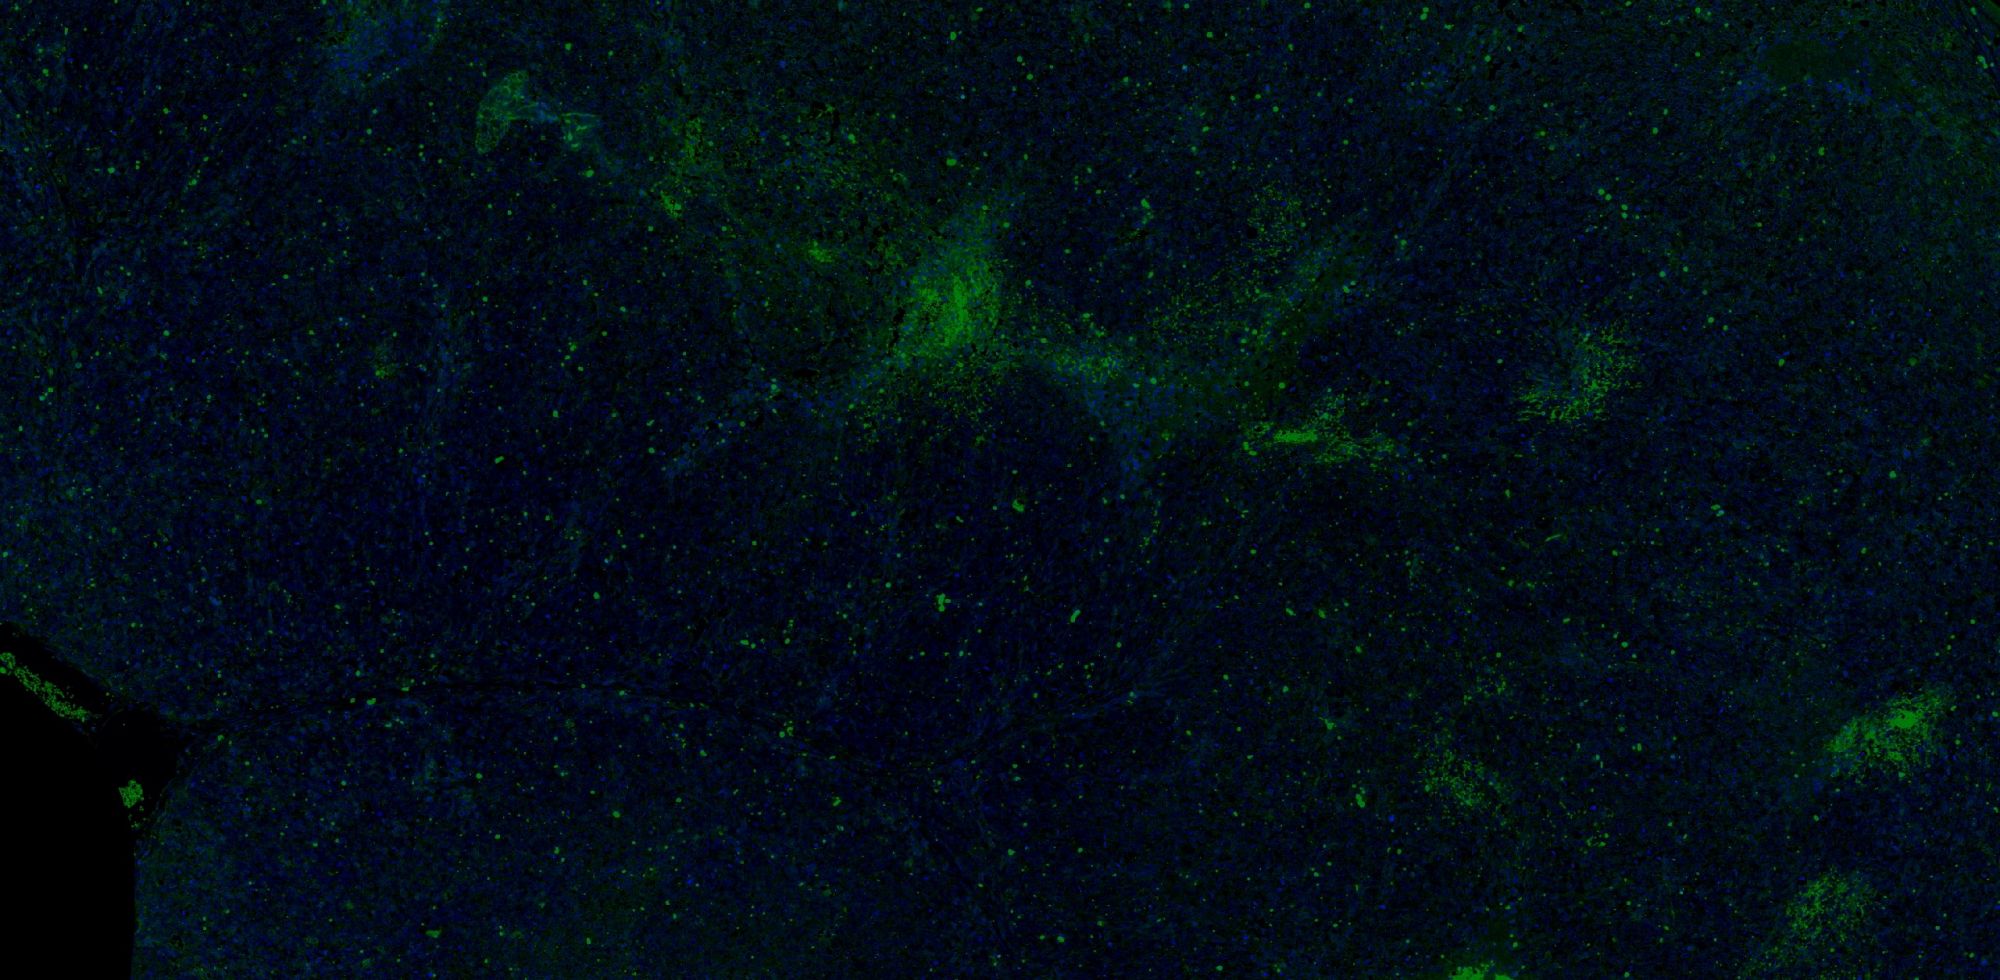

實驗介紹

【技術原理】

免疫學的基本反應是抗原-抗體反應。由于抗原抗體反應具有高度的特異性,所以當抗原抗體發生反應時,只要知道其中的一個因素,就可以查出另一個因素。免疫熒光技術就是將不影響抗原抗體活性的熒光色素標記在抗體(或抗原)上,與其相應的抗原(或抗體)結合后,在熒光顯微鏡下呈現一種特異性熒光反應。

【實驗流程】

案例展示